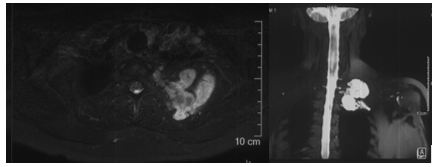

病变部位MRI

病变位于第2后肋,其后方为肩胛骨,并与锁骨下血管、臂丛神经解剖毗邻